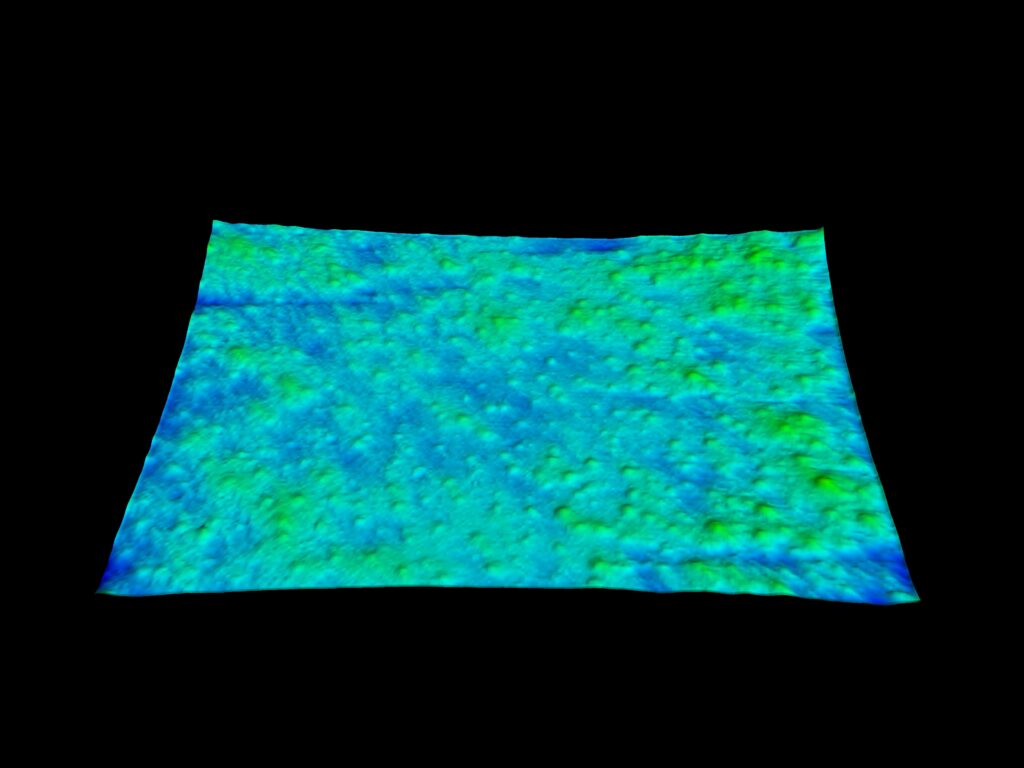

You can also perform 3D acquisitions of the skin surface. Thanks to a technique called stereo photometric, the C-Cube analyses several images under different lighting conditions. The software estimates surface normals. Combined with geometric calibration, it produces elevation information at every pixel.

Roughness evaluation

The C-Cube is undeniably the best option for evaluating even the most subtle changes. Beyond measuring pimple elevation, it is able to observe very small signs of acne before they worsen with inflammation. This is equivalent to measuring the texture of the skin, invisible to the naked eye.

In 2D, this involves color analysis, followed by shape identification to eliminate other objects and retain only the pores. The results are images processed in black and white. You also get a spreadsheet with the median area, median diameter and pore density of each image.

3D analysis provides an additional dimension of pore depth. The 3D approach improves the sensitivity of pore detection. It can then be used to assess the depth of the pores and their possible filling.